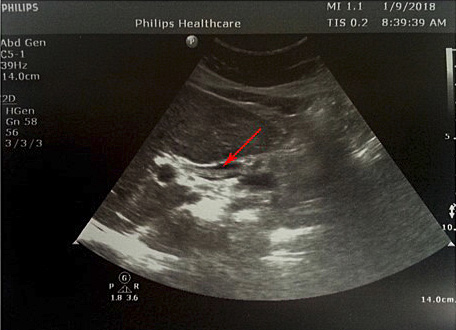

1 pav. Prisipildymo defektas (helmintas) BTL (pažymėta rodyklėmis), nesant echogeninio šešėlio

Atlikus ultragarsinį pilvo tyrimą, konstatuota, kad tulžies pūslė pašalinta, BTL 0,8–1,0 cm pločio. Jo spindyje pastebėtos hiperechogeniškos masės (0,6–0,8 cm skersmens), distaliniame gale susiliejančios į didesnes sankaupas (1, 2 pav.). Kitų vidaus organų ir struktūrų matomų patologinių pokyčių nenustatyta.

Sergant tulžies latakų askaridoze, kraujo tyrimai gali atitikti normos ribas. Tokiu atveju įtarti patologiją padeda paciento nusiskundimai, išsami ligos ir gyvenimo anamnezė (kelionės, namų aplinka, valgymo įpročiai ir sąlytis su dirvožemiu). Specifinių (ligą diagnozuojančių) laboratorinių tyrimų askaridozei nustatyti nėra. Tiksliai diagnozuoti parazitų invaziją į žarnyną, kai laboratoriniai tyrimai nepatologiniai, galima identifikavus askaridžių kiaušinėlius paciento išmatose [3, 27]. Kirmėlių migraciją į tulžies latakus galima nustatyti atlikus ultragarsinį tyrimą. Dažnai ultragarsu pastebimas prisipildymo defektas BTL. Jis būna pailgos arba cirkuliarios formos, be tulžies latakų akmenims būdingo šešėlio – artefakto. Dėl šios priežasties ultragarsu stebimas prisipildymo defektas dar vadinamas „minkštu“ radiniu (1, 2 pav.). Nors ultragarsinis tyrimas vertinamas kaip jautrus ir specifiškas (atitinkamai 40–70 proc. ir 90 proc.), tyrimo kokybė priklauso ir nuo tyrėjo patirties. Tulžies latakuose esant oro po buvusių intervencijų arba kirmėlių maceracijos metu, kai kirmėlė negyva, ji gali būti nepastebėta [2, 3].